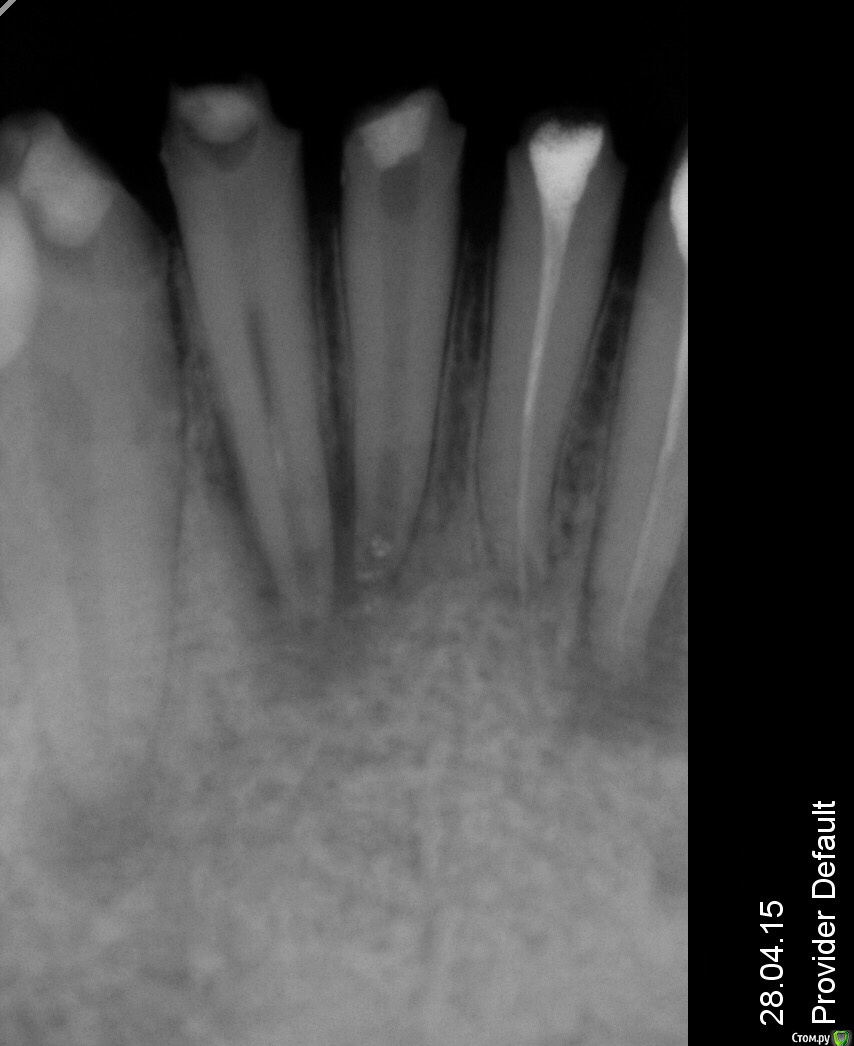

Сашуля Опубликовано 8 декабря, 2016 Поделиться Опубликовано 8 декабря, 2016 (изменено) Здравствуйте уважаемые стоматологи.Очень хочется получить совет.Имею хронический периодонтит. Температура 37,3 постоянно, впрочем, это мне не мешает.Первое фото. Когда обнаружили периодонтит. 2013 год.Второе фото-в процессе лечения.Мне запломбировали каналы, постави вкладку, налили пластиковую временную коронку и отправили в свободное плавание. Зуб никак не беспокоил.Наблюдалась, делала снимки с определённой периодичностью. Зуб не беспокоил.Сейчас настал решающий момент. Последние два снимка были сделаны сегодня. Сторона с проблемным зубом ноет, непонятно, что это болит, толи соседние зубы, толи периодонтит беспокоит. Боль усиливается к вечеру. При надавливании на проблемный зуб острая боль. При внешнем осмотре всё в норме.Вообще грозятся удалять или сделать Гемисекцию. Чего мне ожидать, может быть можно по данным снимкам чтото выяснить.Спасибо. Изменено 8 декабря, 2016 пользователем Сашуля Ссылка на комментарий

Сашуля Опубликовано 9 декабря, 2016 Автор Поделиться Опубликовано 9 декабря, 2016 (изменено) Можно убрать проблемную половину зуба, но со второй половиной ничего толкового не сделать потом. тупиковый путь. У вас 2 варианта.извлечение вкладки и перелечивание зуба либо удаление и имплантация. +1 +Всем спасибо за ответ.Сделали мне снимок и обнаружилась киста. В клинике хирургов не оказалось, один в отпуске второй в Америке. Сказали либо удалять кисту и попробовать оставить зуб либо удалять зуб.Сейчас попробую извлечь снимки. Или если болит с кистой, то только удалять? Изменено 9 декабря, 2016 пользователем Сашуля Ссылка на комментарий

Сашуля Опубликовано 12 декабря, 2016 Автор Поделиться Опубликовано 12 декабря, 2016 (изменено) Увы, киста была слишком большого размера, 7 - 8 мм, не подлежащая лечению. Всё, сильно воспалённое, удалили.Но, у всех специалистов разное мнение.... Будет имплант. Изменено 12 декабря, 2016 пользователем Сашуля Ссылка на комментарий